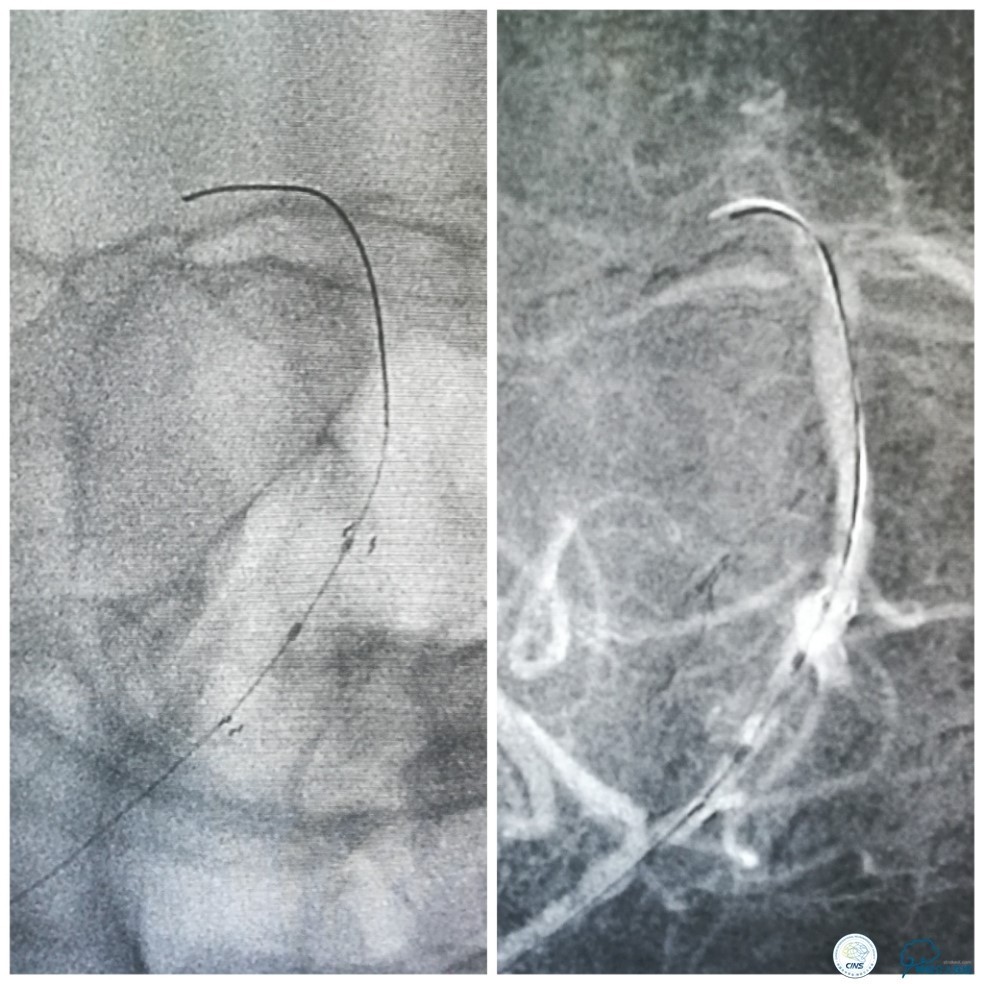

外院DSA(图3):右椎动脉起始处显示不清,右椎动脉V4段重度狭窄,左椎动脉V2-3段经侧支代偿显影。

图3